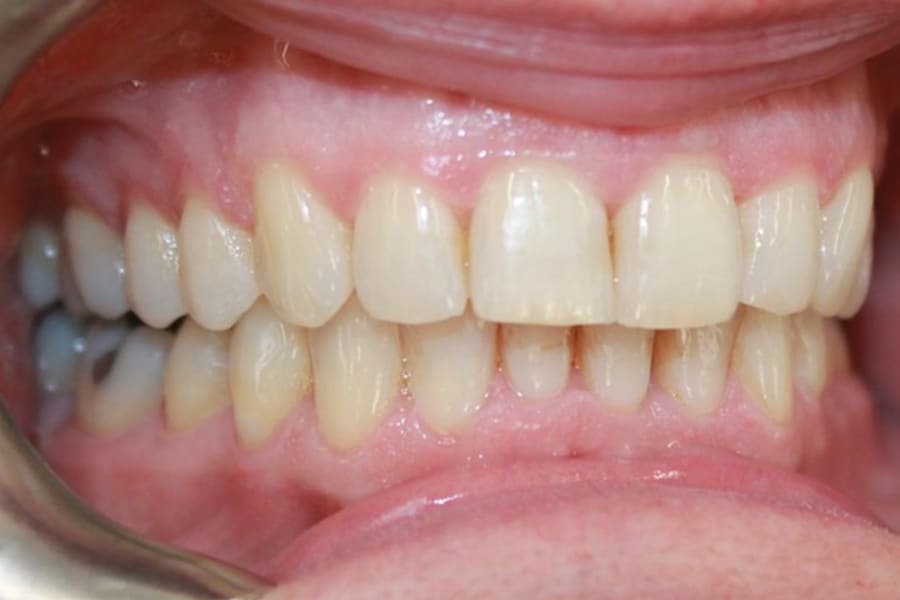

A 54-year-old woman presented with a chief complaint of teeth crowding. After comprehensive digital records were obtained, ClearCorrect® aligner therapy (Straumann, clearcorrect.com) was chosen with an anticipated 12-month treatment duration. The patient exhibited moderate anterior crowding, a class II molar relationship, and narrow arches. The treatment plan aimed to resolve the class II discrepancy, expand the arches, and establish proper anterior alignment. A total of 25 active aligners plus two retention aligners were prescribed. Attachments were selectively placed on the maxillary and mandibular canines to premolars, minimizing bulk while maintaining control over torque and posterior alignment. The patient was instructed to wear class II elastics full-time, which was crucial to achieving molar correction and arch expansion. Her outstanding compliance with class II elastics contributed to a significant improvement in molar position and transverse arch development. After completing the active phase, the patient transitioned to retainers to ensure long-term stability of the results. Given the patient’s initial class II occlusion, monitoring retention was emphasized to prevent relapse. The patient was extremely pleased with the outcome, demonstrating a broadened smile and improved occlusal function. This case underscores the effectiveness of ClearCorrect’s aligners in adult patients, particularly when combined with compliant elastic wear and targeted expansion strategies.